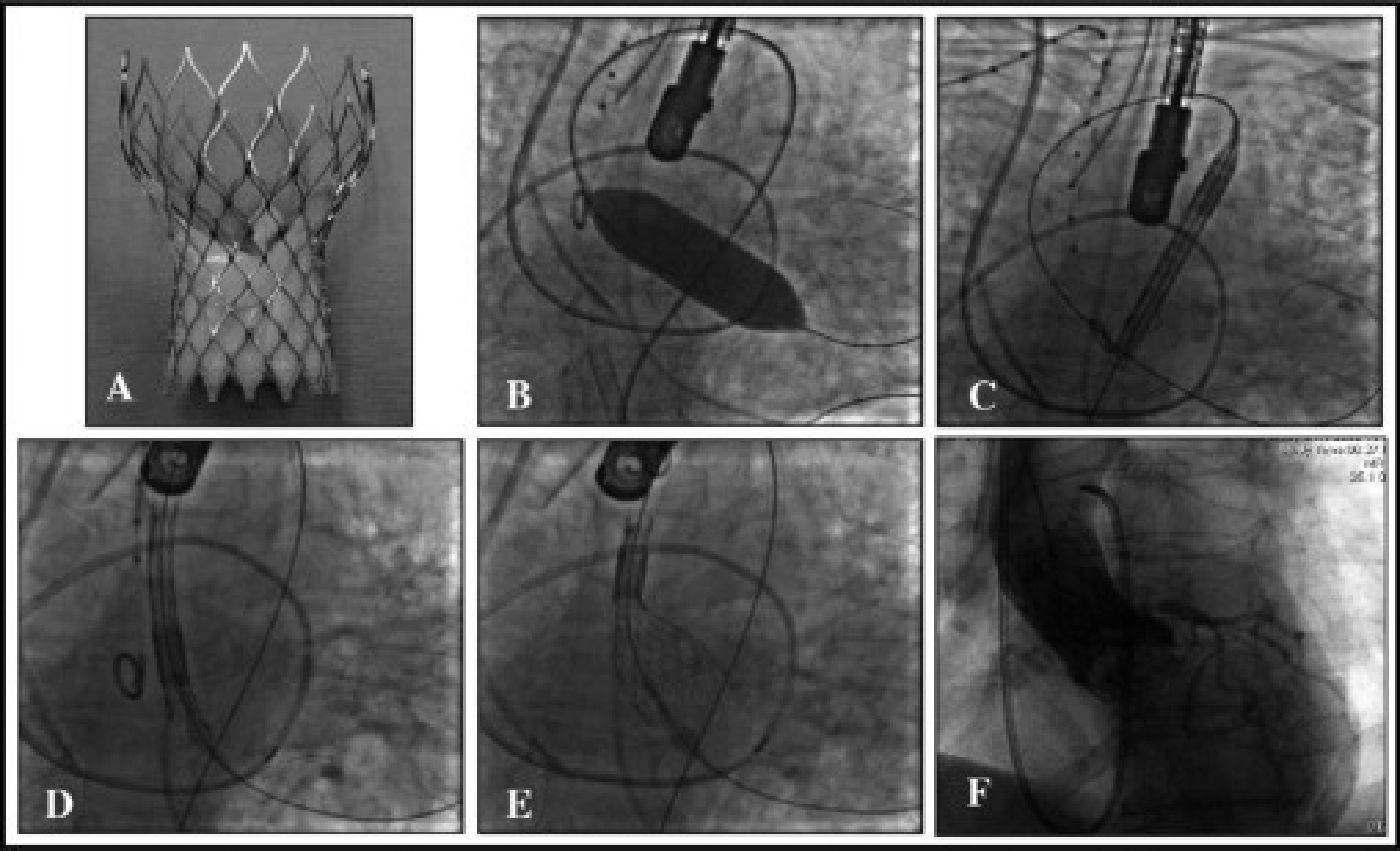

Steps in Deploying the Core Valve Revalving System

A) Core Valve Revalving System;

B) Balloon Valvuloplasty;

C&D) Passing the Core Valve from the aorta across the aortic valve;

E) Deploying the artificial valve

F) Fully deployed artificial valve